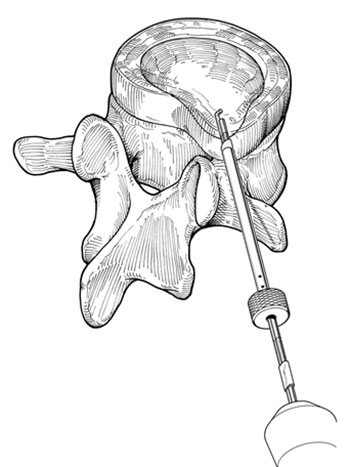

Após a introdução do fio guia procede-se com o dilatador, seguido da cânula, para finalmente poder introduzir o microressector, aparelho com o qual é realizada a ressecção do conteúdo do disco (Fig 5 a-e).

Fig. 5a

Fig. 5b